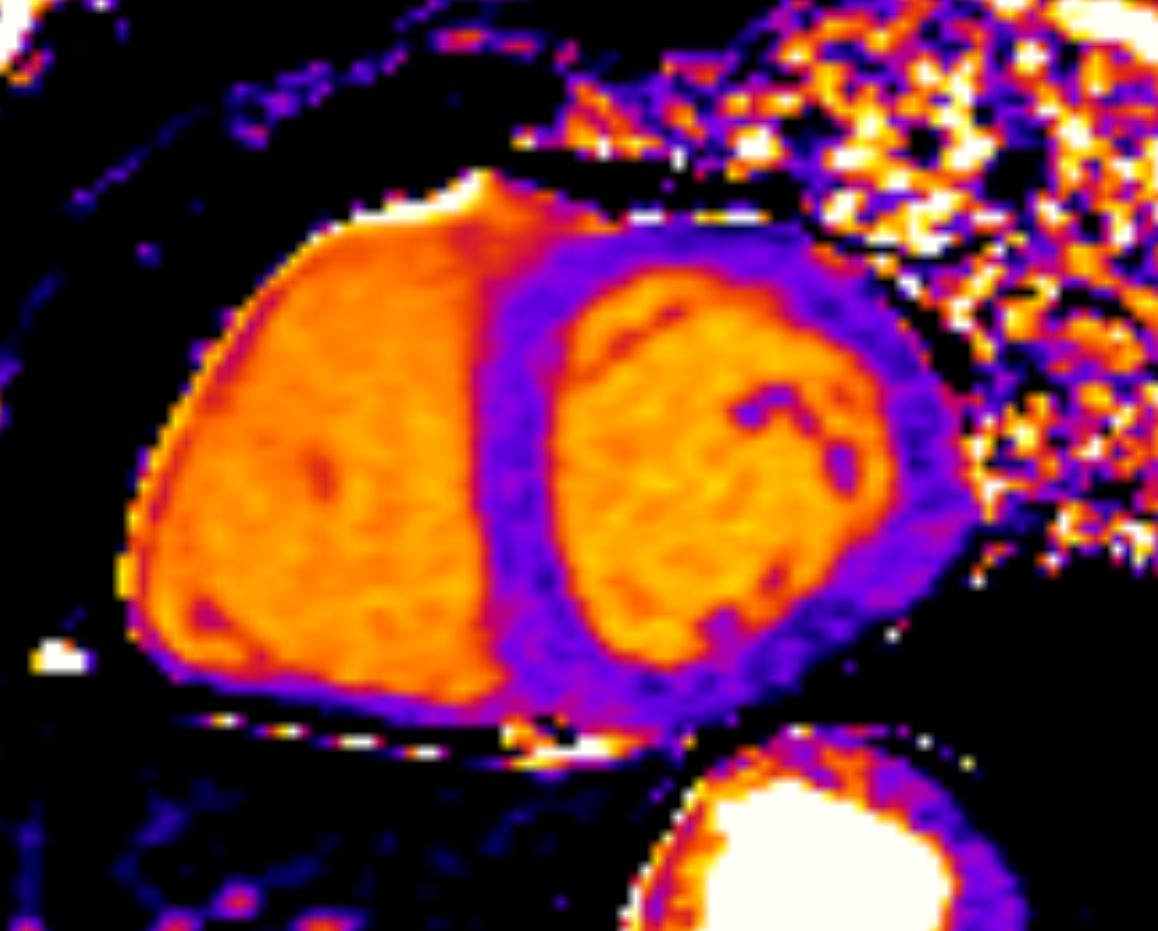

Фиброз миокарда характеризуется накоплением внеклеточного матрикса в миокарде и связан с рядом сердечно-сосудистых заболеваний (ССЗ), включая инфаркт миокарда, а также дилатационную и гипертрофическую кардиомиопатии.

Наиболее точным методом количественной оценки фиброза миокарда является магнитно-резонансная томография (МРТ). Применение T1-картирования и расчёта внеклеточного объёма миокарда (extracellular volume (ECV)), позволяет оценить интерстициальный фиброз, увеличение

которого является маркёром ремоделирования миокарда.

В исследовании MESA (The Multi‐Ethnic Study of Atherosclerosis) изучили взаимосвязь между курением и интерстициальным фиброзом миокарда, определяемым с помощью МРТ сердца, а также гендерные различия в этой связи.